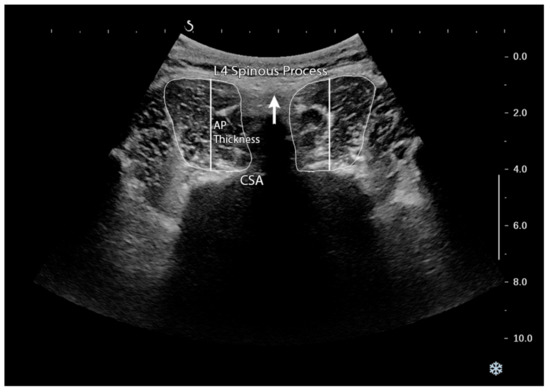

2.2. Procedure